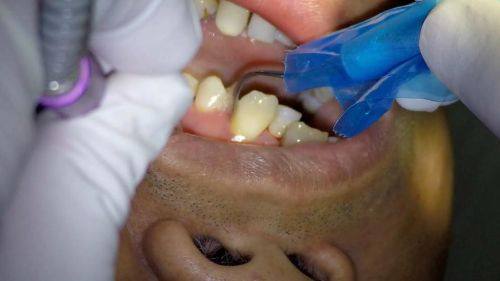

牙周治疗、牙周牙髓病治疗:能够精细诊断牙周与牙髓病变,采用规范的诊疗手段控制炎症、修复受损组织,缓解口腔疼痛不适,帮助患者修复口腔健康。

患者张先生 牙周治疗项目“我一直受慢性牙周炎困扰,牙龈经常出血红肿,杨医生仔细检查后制定了针对性的治疗方案,经过一段时间的治疗,症状明显好转,医生态度也特别耐心,会解答我所有的疑问。”